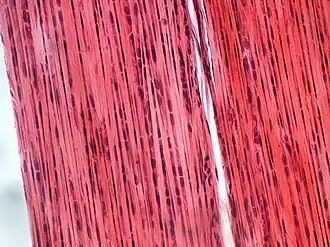

Dense connective tissue, also called dense fibrous tissue, is a type of connective tissue with fibers as its main matrix element.[1] The fibers are mainly composed of type I collagen. Crowded between the collagen fibers are rows of fibroblasts, fiber-forming cells, that generate the fibers. Dense connective tissue forms strong, rope-like structures such as tendons and ligaments. Tendons attach skeletal muscles to bones; ligaments connect bones to bones at joints. Ligaments are more stretchy and contain more elastic fibers than tendons. Dense connective tissue also make up the lower layers of the skin (dermis), where it is arranged in sheets.[2] In addition, the sclera contains dense connective tissue[3]

It is classified as either dense regular connective tissue or dense irregular connective tissue.[4]